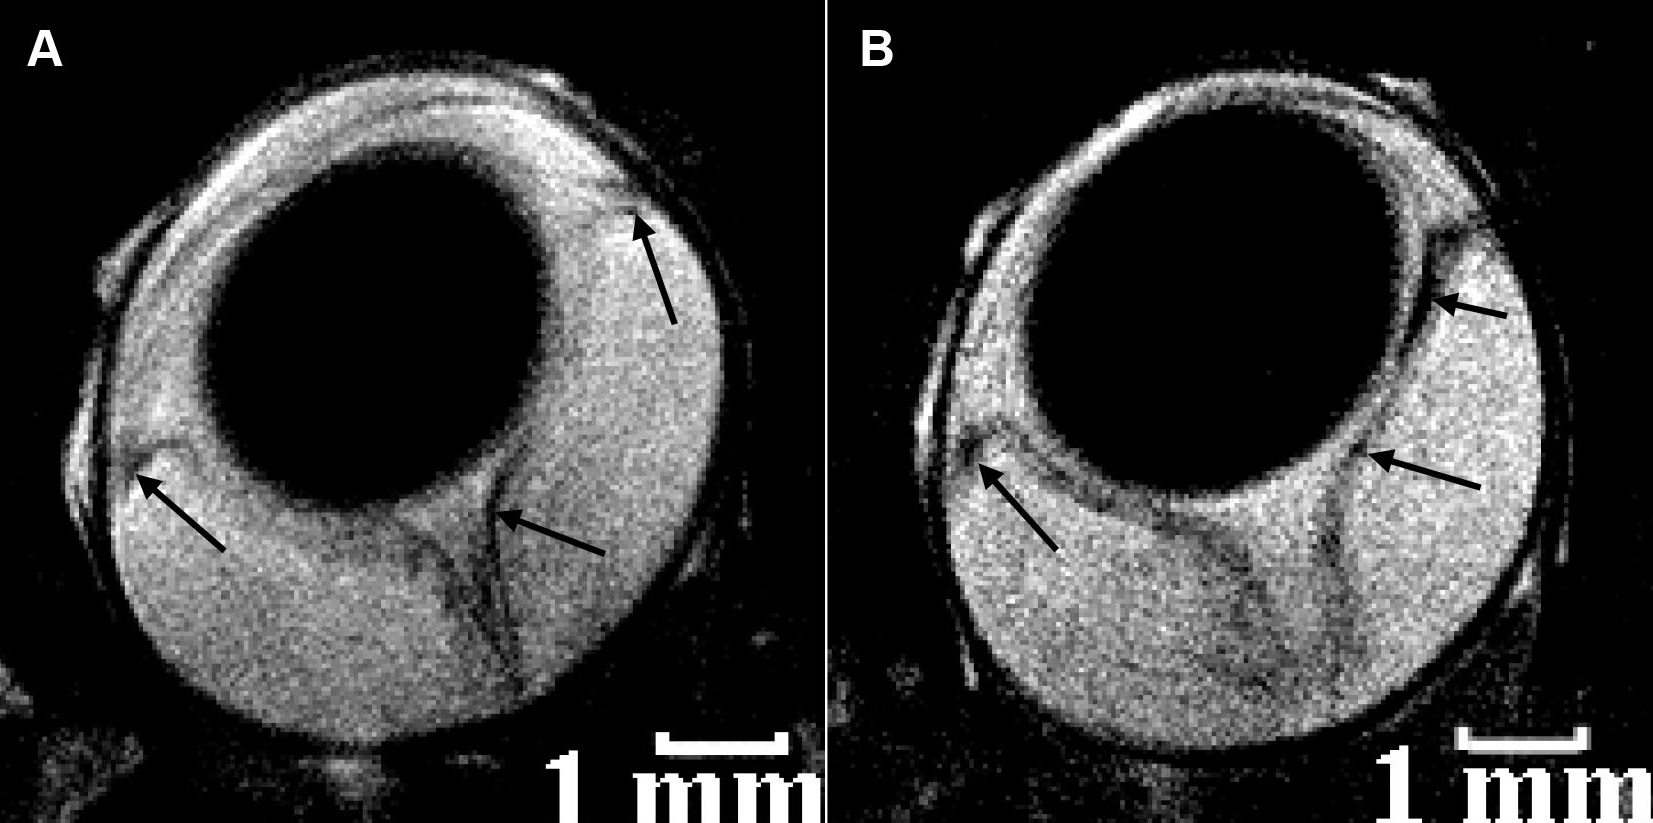

Figure 5. Selected in vivo magnetic resonance imaging transverse sections of rat eyes at the peak of experimental autoimmune uveitis. Sites of decreased signal intensity (arrows) in the region of the retina, iris, and ciliary body are clearly visible. The rats were injected intravenously in the tail vein 4 h before magnetic resonance imaging (MRI) with A 0.9% physiologic saline and B 300 μM Sinerem solution in 0.9% physiologic saline. The spatial resolution of both MRI images is 40×40×700 μm3, and their acquisition time was 25 min. All MRI images in this figure are T2-weighted. The images were reproduced from [39] with permission from the International Society of Magnetic Resonance.